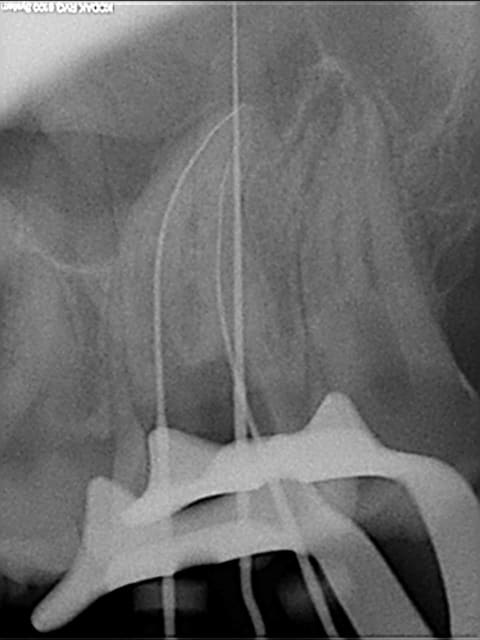

les radios

R1 tjqc9c - Eugenol

R8 vojabs - Eugenol

01/10/2008 à 17h48

autre cas assez ou il est impossible de compacter avec un mc spadden correctement le 1/3 apical des cannaux vestibulaires (déjà posté)

R1 vgvv1w - Eugenol

R5 vdlpi4 - Eugenol